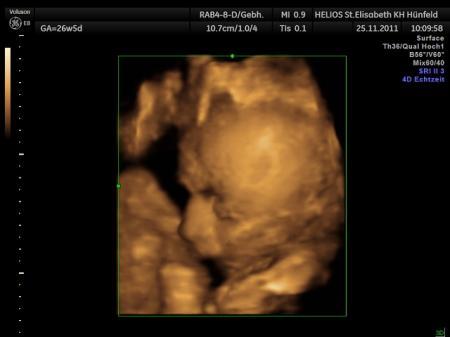

Möchte euch meine Maus vorstellen..

...voll verliebt...:D

leider liegt sie mit der linken Gesichtshälfte an die Plazenta gedrückt..*g* scheint kuschelig zu sein

Das ist ja ein tolles Bild :) Echt knuffig :) Krass wie man schon die Gesichtszüge erkennen kann... Ich hoffe meine zeigt sich am Freitag auch :)

Ohhhh wie süß und den Finger an der Nase - das ist ja knuffig :D Unser kleiner Sonnenschein kuschelt mit der rechten Seite immer meine linke Bauchdecke bzw. Seite - scheint Ihm da auch super zu gefallen :D Alles Gute weiterhin für Euch :D VLG. Annabelle, Oli und klein Eric im Bauchi